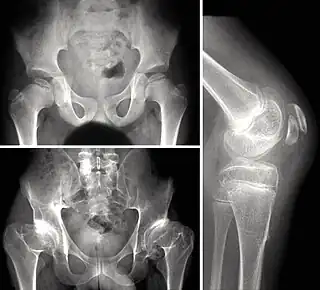

Las pruebas radiológicas suelen ser la clave del diagnóstico.[2] Es recomendable confirmar el diagnóstico con una prueba genética que confirme el tipo de displasia. Los centros de osificación epifisarios suelen aparecer tarde, (retraso de edad ósea), y aparecen con una forma irregular, o incluso fragmentados, en las formas más graves. Muy importante comprobar que la afectación es múltiple.

• Caderas: La epífisis proximal del fémur se deforma, aplanándose, con parecido a una coxa vara. Aparece artrosis precoz, aunque sin quistes periarticulares.

• Rodillas: Cuadrangulación de los cóndilos del fémur. También es frecuente el genu valgo, (pudiendo ser planteable una osteotomía correctora).